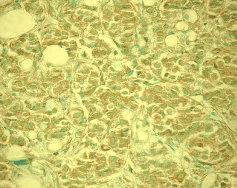

Detection of human MDM2 by staining paraffin sections. Sample: Breast carcinoma. Primary antibody: Anti-MDM2 (Ab-3) Mouse mAb (4B11) (Cat. No. OP143) (2.5 μg/ml). Detection: DAB